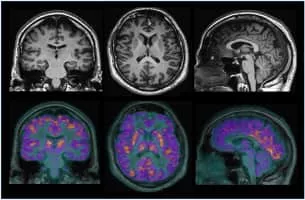

Neuroimaging photograph

Neuroimaging

Neuroimaging or brain imaging is the use of various techniques to either directly or indirectly image the structure, function, or pharmacology of the nervous system. It is a relatively new discipline within medicine, neuroscience, and psychology.